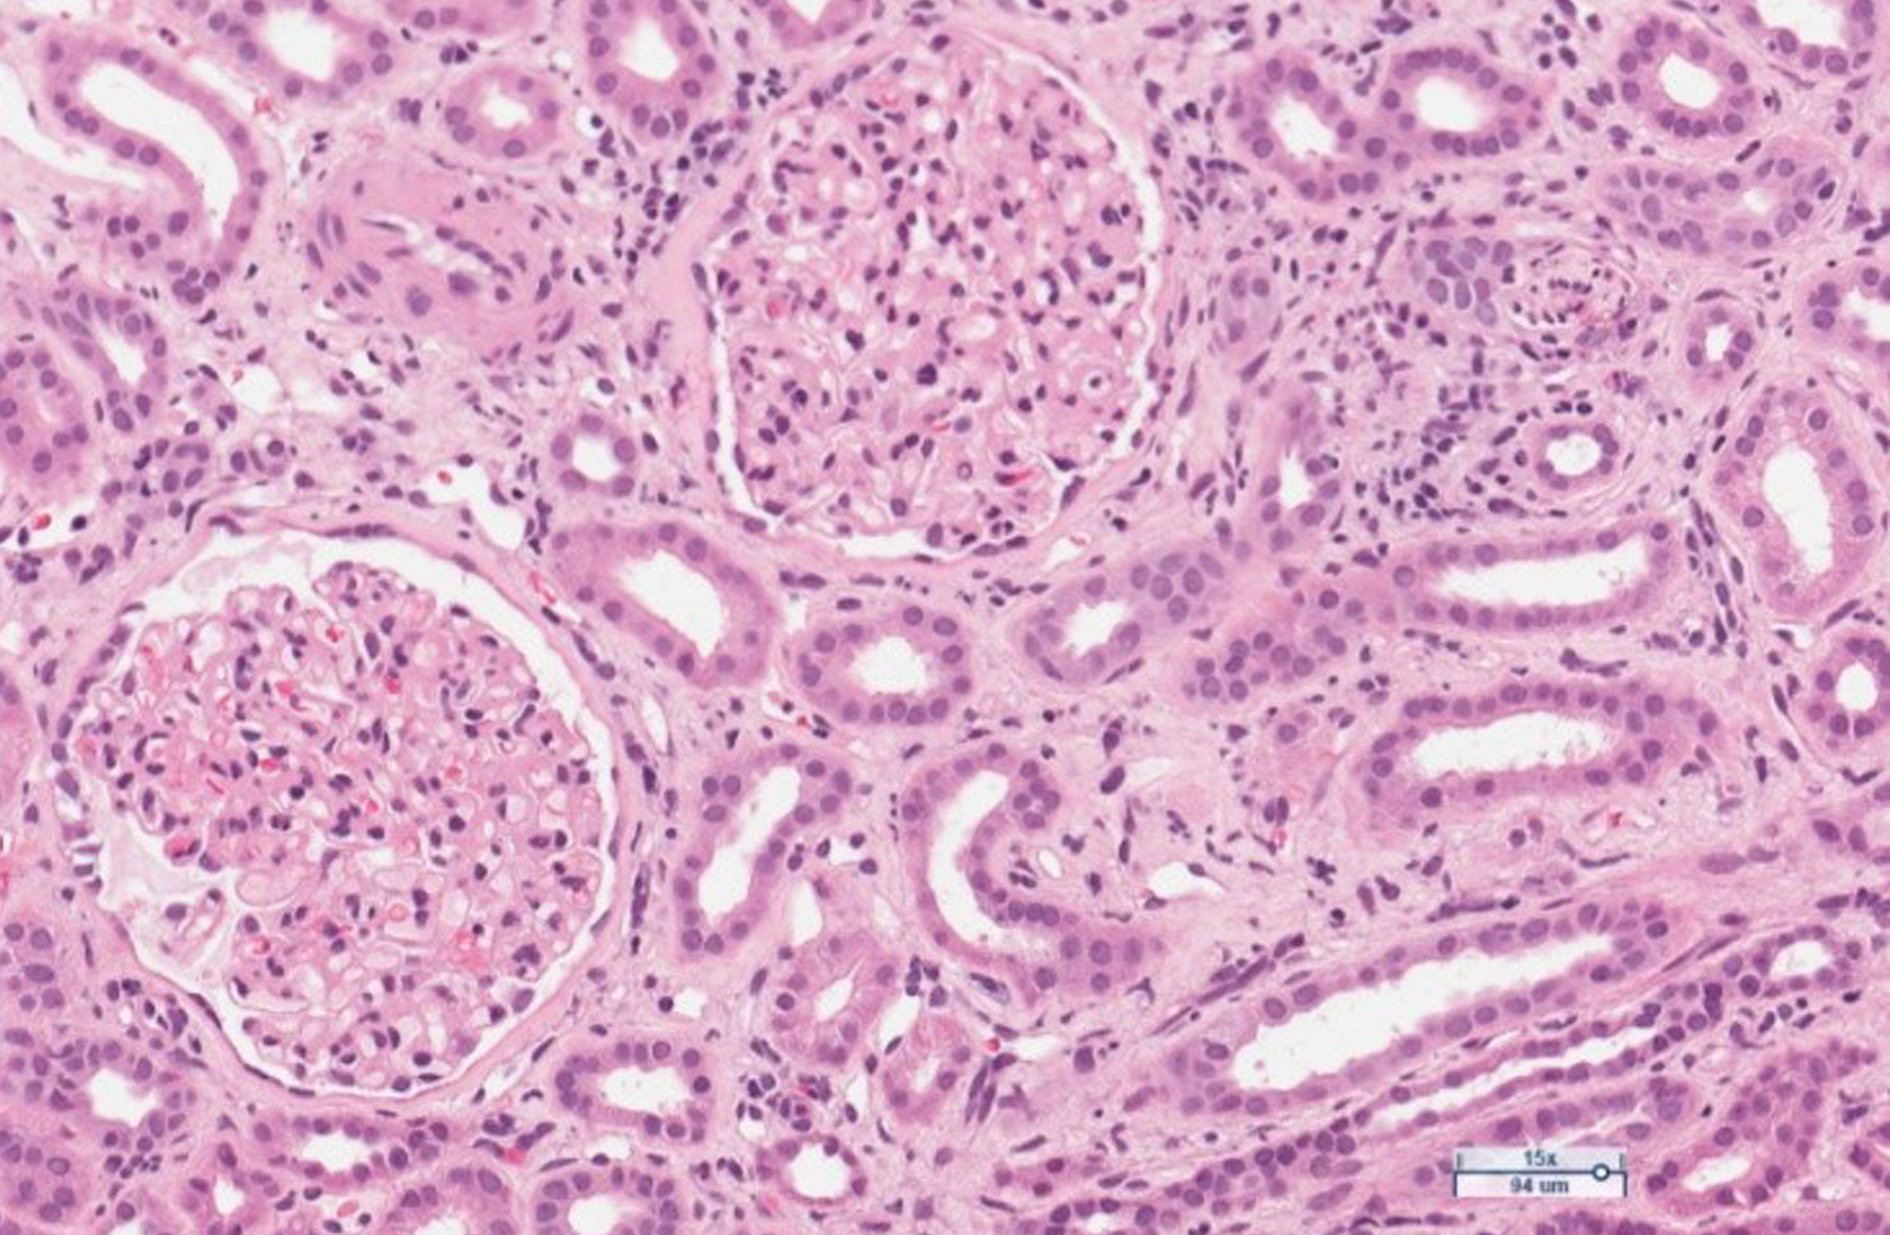

Figure 1. Limited foci of mixed inflammatory infiltrates with mononuclear leukocytes, plasma cells, neutrophils and eosinophils, with patchy fibrosis in the interstitium. Moderate arteriolar sclerosis. Glomeruli are unremarkable. H&E stain.

The course of interstitial nephritis can be acute and chronic. The classic form of acute IN is not dose related [7]. The most common symptoms are fever, rash, and lymphadenopathy. Laboratory tests may include pyuria and eosinophilia [7,8]. Another form of the disease manifests itself as a severe chronic, progressive, asymptomatic interstitial nephritis. It is thought to result from a cell-mediated response. The disease is difficult to recognize because it is asymptomatic and is most commonly found when blood creatinine and urea levels increase [8]. Kidney biopsy can show chronic IN in up to 58 percent of cases as it reveals chronic inflammatory changes in the interstitial tissue [7]. The biopsies from our patient also revealed the signs of interstitial nephritis. As the biopsy had been performed already sometime after the discontinuation of treatment with mesalamine, the low-activity chronic interstitial nephritis has been stated (Fig.1, Fig.2).